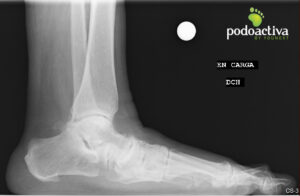

Mujer de 70 años acude refiriendo molestias a nivel del arco interno con evolución de 7 meses y no mejora con reposo ni antinflamatorios.

Se observa pie plano grado IV y lesión del ligamento de Spring. Se realiza exploración biomecánica y se observa una marcha en supinación compensando las molestias del arco interno. Tras el test biomecánico, indican alteraciones en la articulación subtalar y en los elementos estabilizadores del arco plantar.

Finalmente, el diagnóstico es un pie plano adquirido del adulto que cursa con lesión del ligamento de Spring y alteración del músculo tibial posterior.

radiografía ligamento_de_spring

Se comienza con un tratamiento leve a nivel de elevación del arco plantar. La paciente ha generado un pie plano adquirido que no habría conseguido soportar de inicio tratamientos ortopodológicos algo más agresivos.